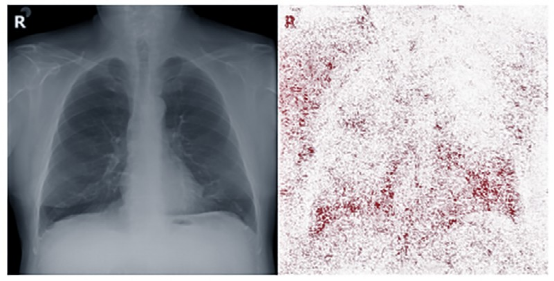

多家医院公开了COVID-19患者的X射线照片(被标记为COVID-19阳性),美国国立卫生研究院在大流行之前收集的肺部图像库提供了未感染COVID-19的X射线数据(被标记为COVID-19阴性),这些数据在被用作训练时存在无法忽视的误作用,例如,许多X射线会使用字母R来标记一个人身体右侧,从而方便放射科医生正确定位图像与人体的关系,但是不同医院采用的字母R的外观不同,同时,大多数COVID-19阴性图片来源单一,这使得最终使用这些数据训练的模型不仅会根据照片上显示的生物特征进行推断,还会根据图片上字母R的风格与位置进行推断(如图1所示)。

图1 用作训练的X射线图片

帮助DeGrave和Janizek确定胸部 X 射线图片上的方向标记(字母R)影响诊断的一种工具是显着性图(Saliency Map),这是一种用颜色编码的图表,显示计算机在推断时最关注图像的哪一部分。如图2所示。